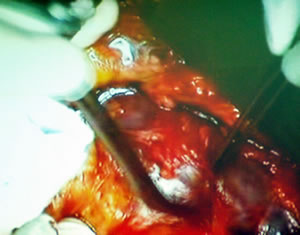

Вскрыто забрюшинное пространство. Оператор выделяет сосудистую

ножку почки.

Сосудистая ножка почки частично выделена.